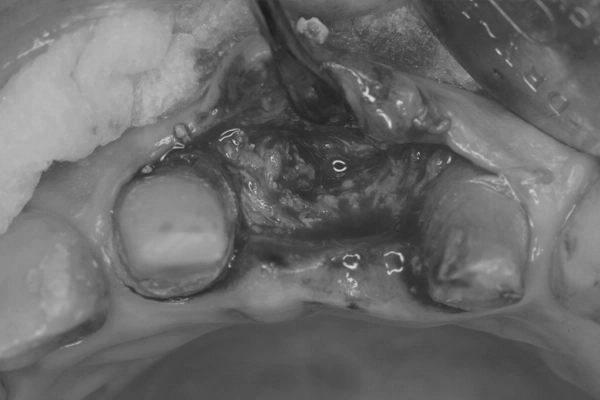

リッジプリザベーション後、骨が十分に成熟したため待時埋入を行いました。

埋入時の様子